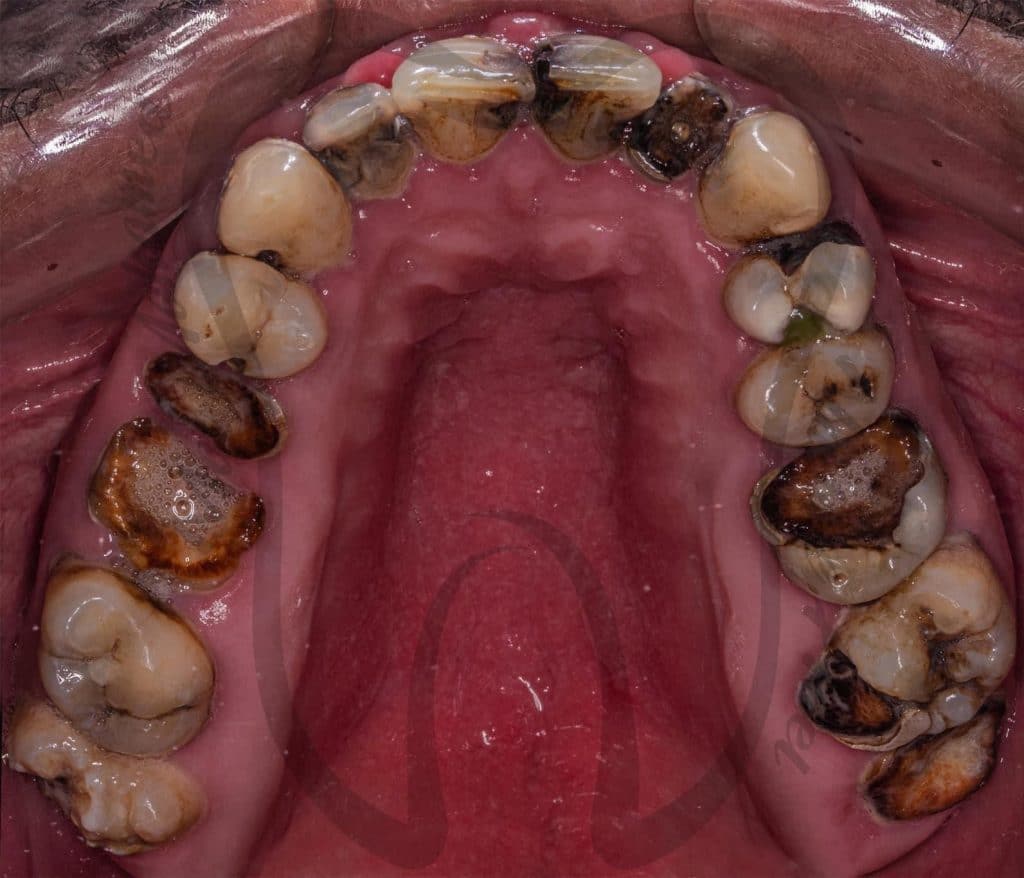

Graduation Case 🎓🎓

5th year student, PUA, Egypt

This case has been done together with my partner Dr Mai Marzouk

Our treatment plan included:

📌 10 Extractions

📌Full Mouth scaling and Root planing

📌 12 Endodontic treatment

📌 6 Post and Core

📌 Full Mouth Composite Restoration

📌 20 Unit Zirconium

📌 5 Unit PFM

📌 Lower Arch Class I Metallic RPD